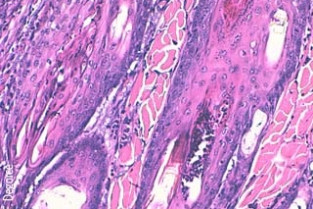

Le Groupe d’Étude en Dermatologie vous propose la première édition des Journées spécialisées de Pathologie Clinique.S'intéressant aux dermatoses éosinophiliques et neutrophiliques, elles seront l'occasion de développer les aspects cliniques mais aussi diagnostiques (avec un accent tout particulier sur la cytologie et l'histopathologie) et thérapeutiques d'entités souvent mal connues ou reconnues. Rejoignez-nous pour faire de ces journées spécialisées un moment d'échange profitable à tous.

- Acquérir des notions générales dans la lecture de lames cytologiques et histopathologiques concernant des dermatoses éosinophiliques ou neutrophiliques.